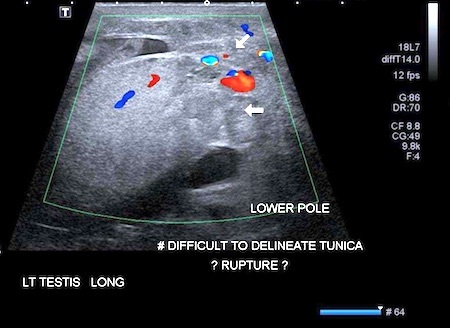

Can Scrotal Gunshot Wound Result in Testicular Injury? [research study]

Persons outside the professional medical world may be unfamiliar with the acronym “SGSW.” A new study may, as a side-effect, help such persons remember that item of information:

“Utility of Preoperative Ultrasound for the Evaluation of Testicular Rupture in the Setting of Scrotal Gun Shot Wounds,” Ryan Powers, Stephen Hurley, Edward Park, Brian McArdle, Patricia Vidal, Sarah P. Psutka, and Courtney M.P. Hollowell, Journal of Urology, epub 2018. (Thanks to Ivan Oransky for bringing this to our attention.) The authors, at John H. Stroger Jr. Hospital of Cook County, and at Northwestern University, report:

“Scrotal Gunshot Wound (SGSW) may result in testicular injury…”